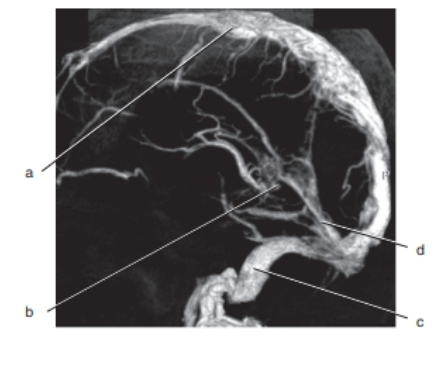

DCE MRA sequences of the mesenteric arteries are performed using:

incoherent GRE

Which letter is the superior sagittal sinus ?

a

What is letter G ?

spleen